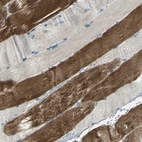

Immunohistochemical staining of human skeletal muscle shows strong cytoplasmic positivity in myocytes.